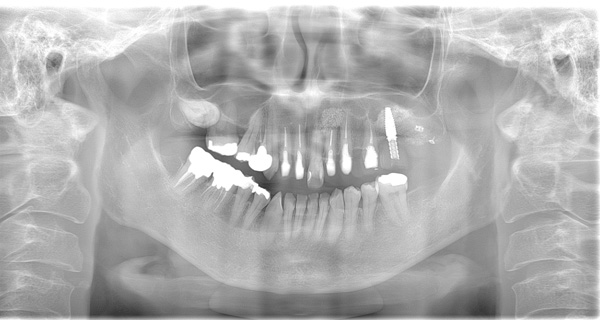

| 年代・性別 | 50代 男性 |

|---|---|

| 主訴 | 右上下の歯が痛い |

| 治療期間 | 約12ヶ月 |

| 費用 | 2,500,000円 |

| 治療内容 | インプラント、骨造成、結合組織移植、セラミック修復 |

| 治療に伴うリスク | インプラント周囲炎 セラミックの破折、脱離 |

*キャンセルポリシーをご一読のうえご予約ください